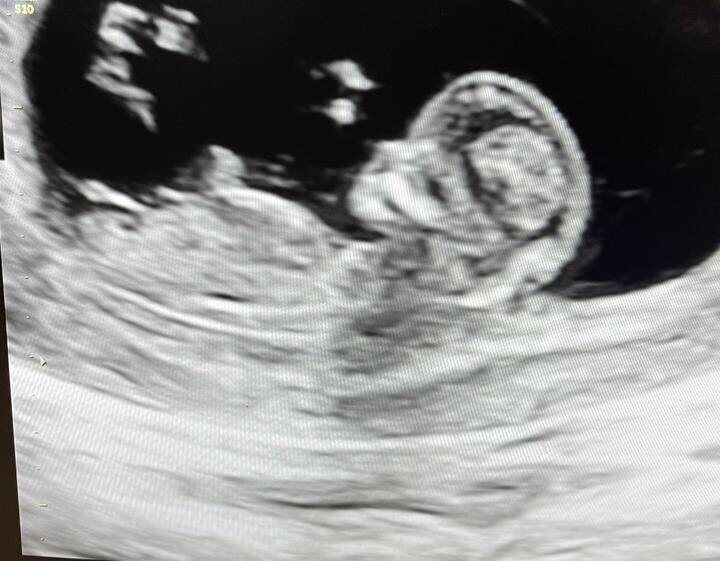

2 фото - узи с Лизой

3 фото - 1 скрининг сейчас